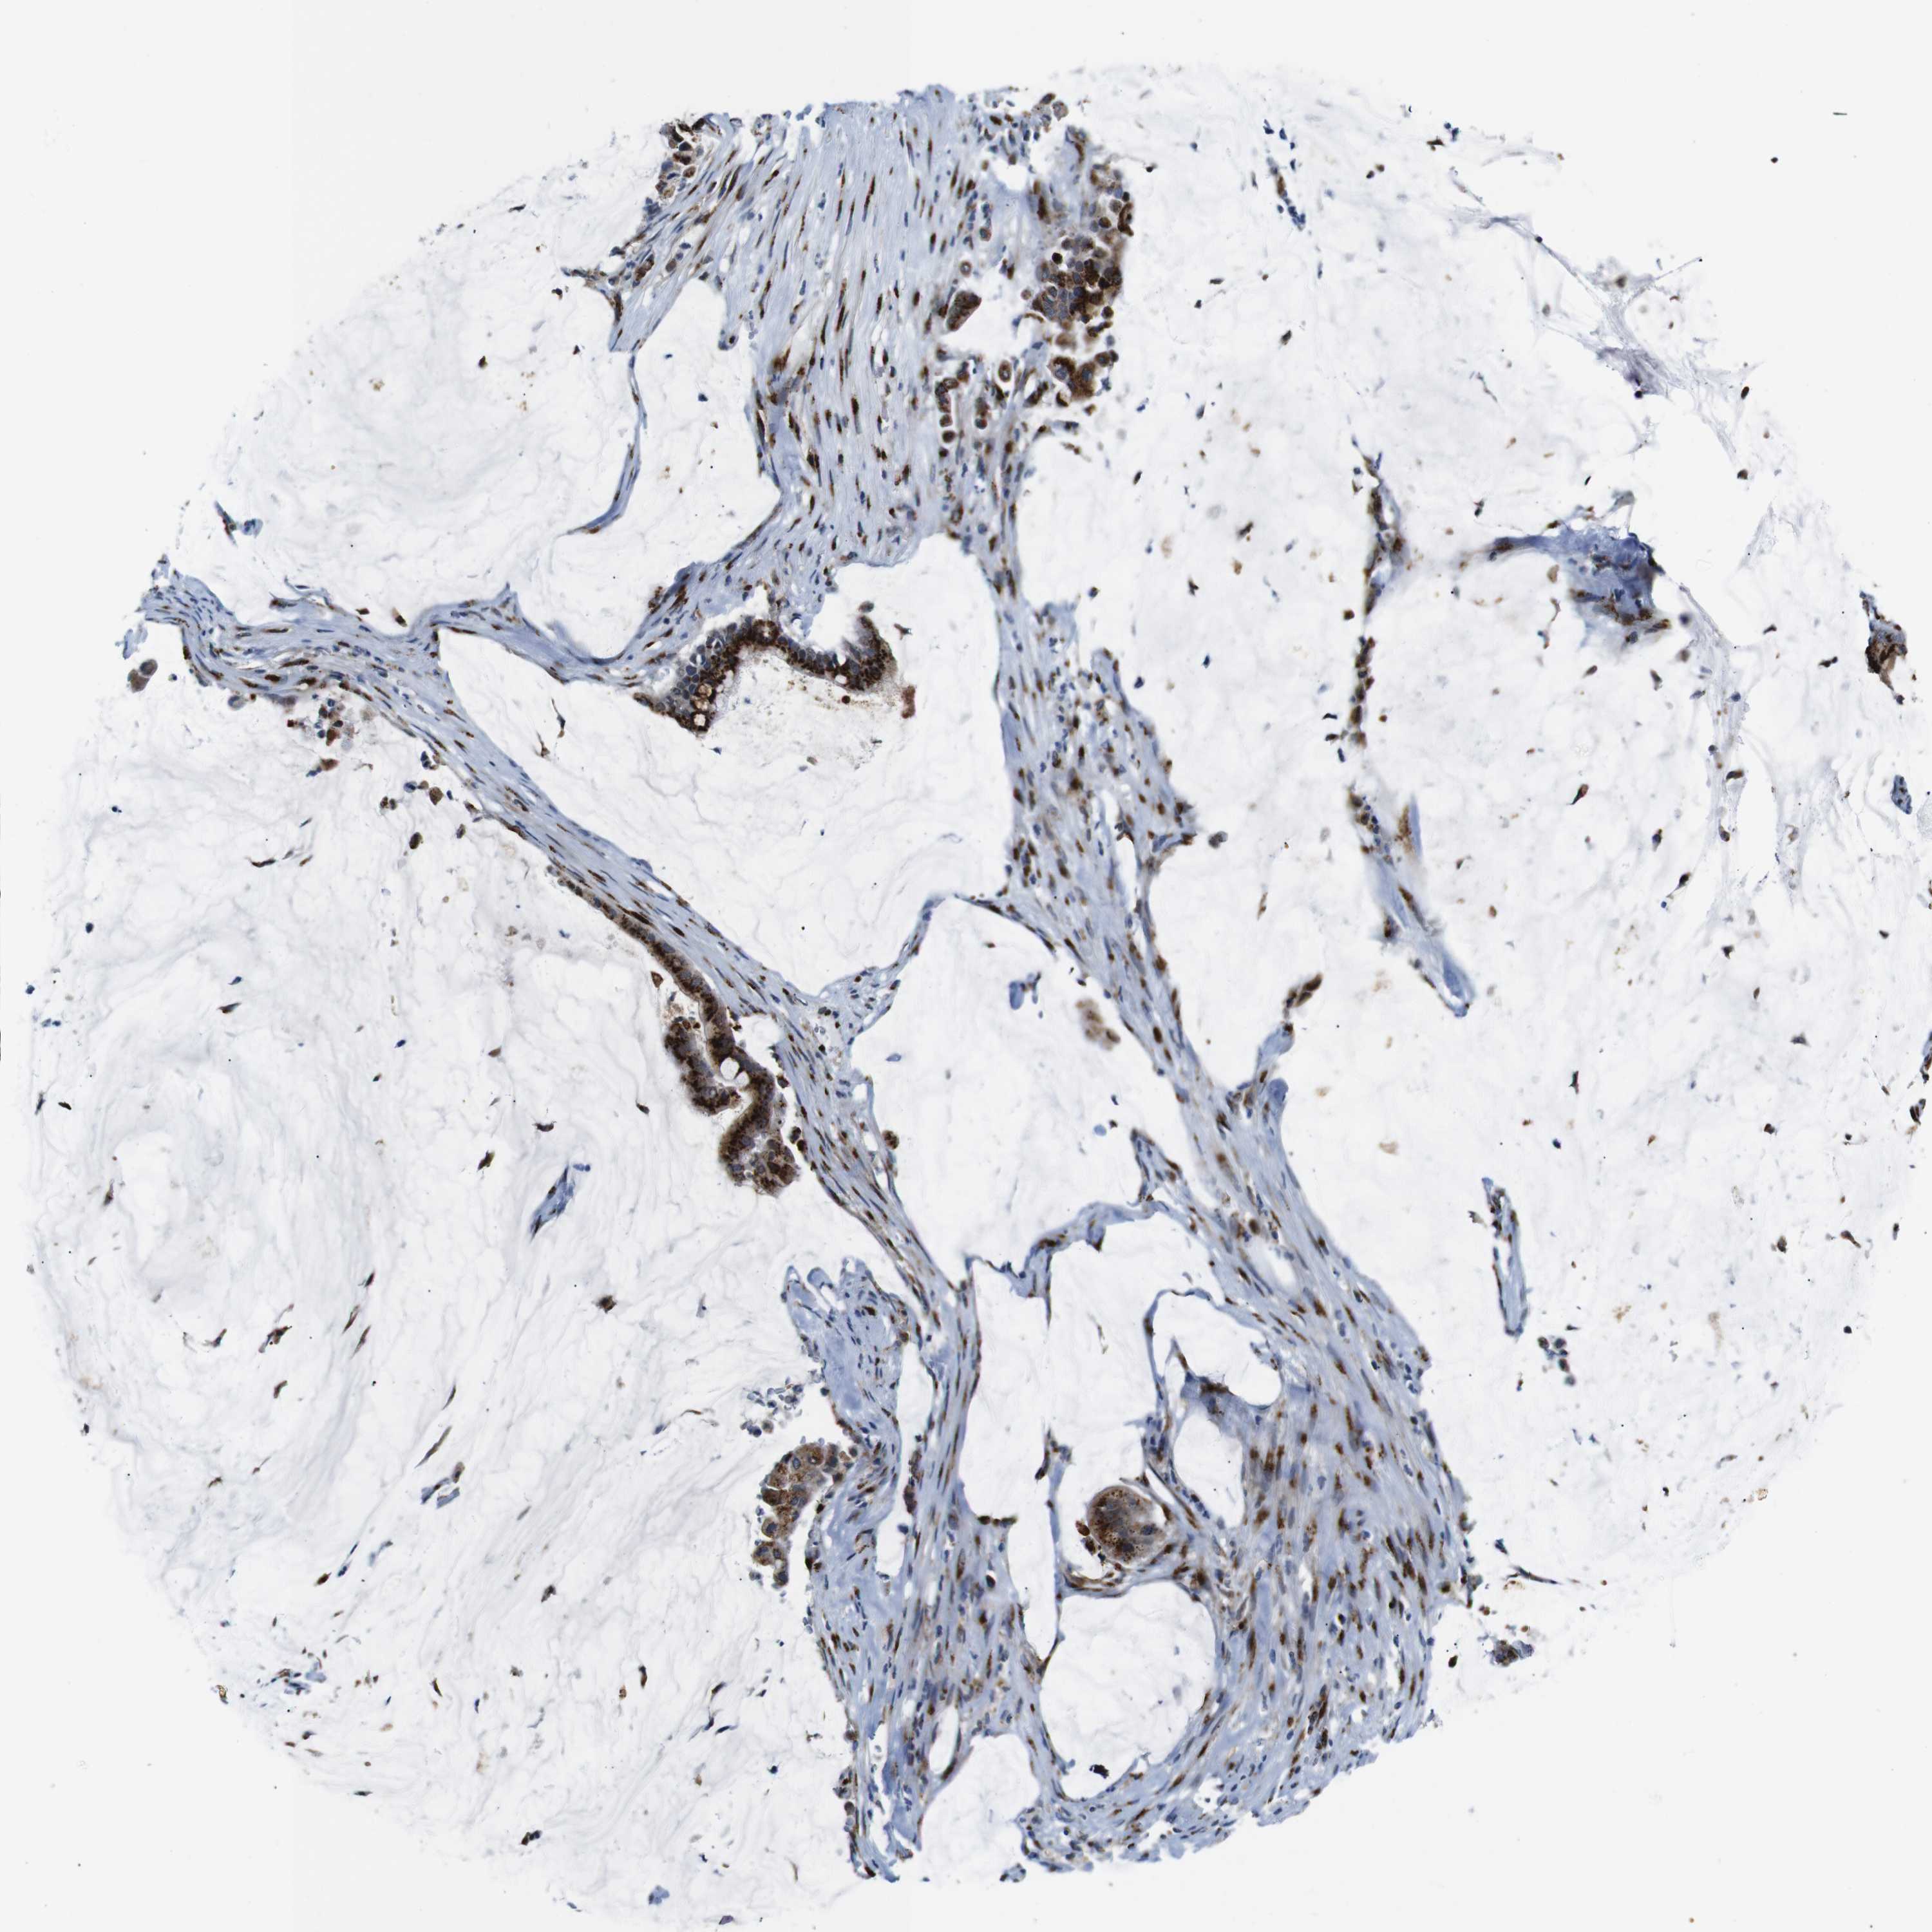

PANCREATIC CANCER - Protein expressioni

A mouse-over function shows sample information and annotation data. Click on an image to view it in a full screen mode. Samples can be filtered based on level of antibody staining by selecting one or several of the following categories: high, medium, low and not detected. The assay and annotation is described here.

Note that samples used for immunohistochemistry by the Human Protein Atlas do not correspond to samples in the TCGA dataset.

Antibody stainingi

Antibody staining in the annotated cell types in the current human tissue is reported as not detected, low, medium, or high, based on conventional immunohistochemistry profiling in selected tissues. This score is based on the combination of the staining intensity and fraction of stained cells.

Each image is clickable and will lead to virtual microscopy that enables deeper exploration of all samples and also displays staining intensity scores, fraction scores and subcellular localization as well as patient and tissue information for each sample.

Antibody HPA012609

Antibody HPA012723

Antibody CAB011489

Staining

High

Medium

Low

Not detected

Intensity

Strong

Moderate

Weak

Negative

Quantity

>75%

75%-25%

<25%

None

Location

Nuclear

Cytoplasmic/membranous

Cytoplasmic/membranous,nuclear

Adenocarcinoma, NOS